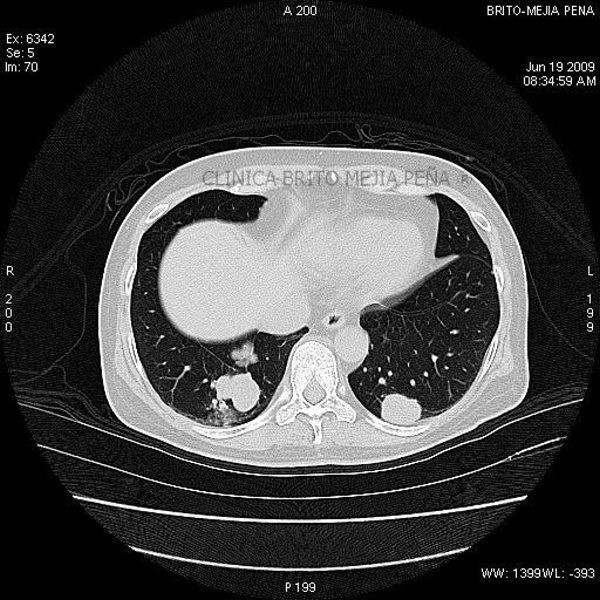

Metástasis pulmonares

Post Image